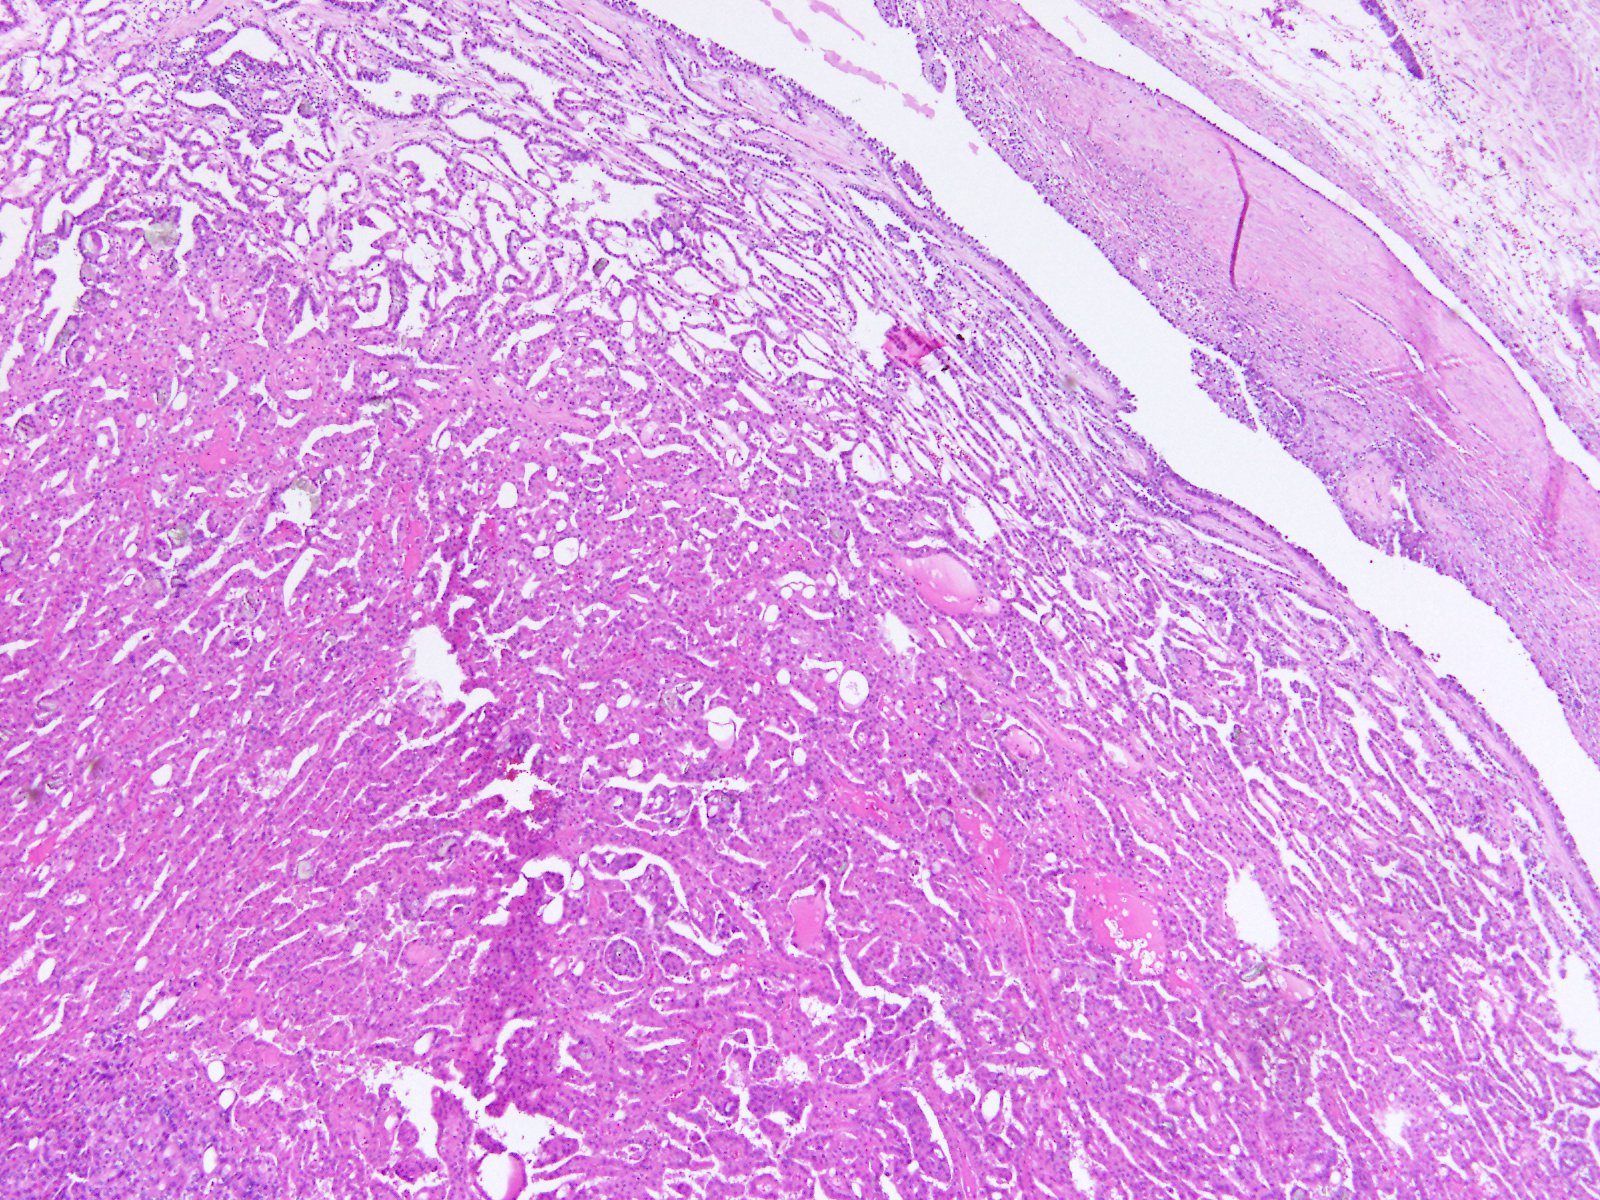

Consensus grade: Acquired cystic disease-associated RCC

User Diagnosis Difficulty Comment

Pathologist 1 Acquired cystic disease-associated RCC Typical

Pathologist 2 Acquired cystic disease-associated RCC Typical

Pathologist 3 Acquired cystic disease-associated RCC Typical

Pathologist 4 Acquired cystic disease-associated RCC Typical

Pathologist 5 Acquired cystic disease-associated RCC Not typical

Pathologist 6 Acquired cystic disease-associated RCC Not typical

Need info of the background kidney tissue

Pathologist 7 Acquired cystic disease-associated RCC Typical

Pathologist 8 Acquired cystic disease-associated RCC Typical

Pathologist 9 Acquired cystic disease-associated RCC Typical

Pathologist 10 Acquired cystic disease-associated RCC Not typical

Pathologist 11 Acquired cystic disease-associated RCC Not typical

Pathologist 12 Acquired cystic disease-associated RCC Typical

Pathologist 13 Acquired cystic disease-associated RCC Typical

Pathologist 14 Renal cell carcinoma, unclassified Not typical

Features of papillar,y clear cell and ACD RCC.

ISUP grade 2

Pathologist 15 Renal cell carcinoma, unclassified Not typical

Pathologist 16 Acquired cystic disease-associated RCC Typical

Pathologist 17 Acquired cystic disease-associated RCC Not typical

More papillary RCC type, however crystaloids are suggestive for ACRD ass RCC. Again, like in previous case.....if there is anamnesis of ESKD....I would vote for ACRD ass RCC

Pathologist 18 Acquired cystic disease-associated RCC Typical